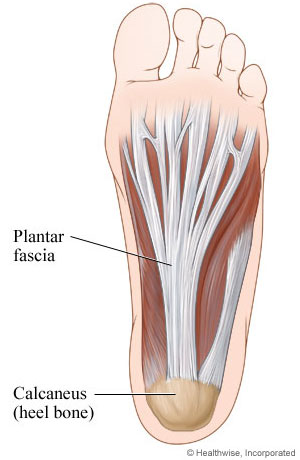

what is plantar fascia?

plantar aponeurosis

plantar fascia

O: medial tubercle of calcaneus

what does the plantar fascia look like?

will band out and bands out to base of toes